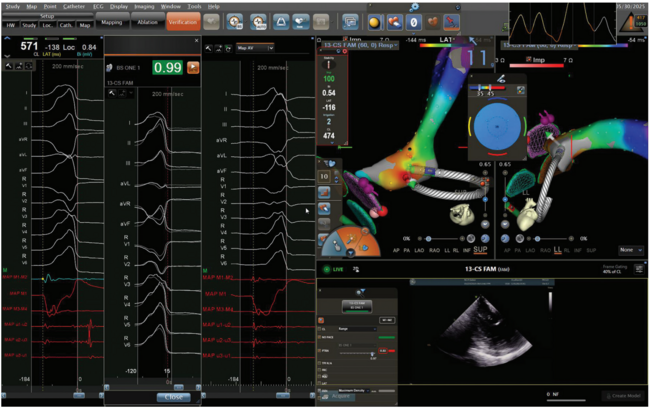

Mapping is employed using a 3-column display (Figure):

- Column 1: Activation map with local electrogram review

- Column 2: PVC template with morphology match (ideally >97%)

- Column 3: Anatomical map and annotation verification

Manual annotation review is strongly encouraged, particularly for fractionated electrograms or poor pace maps, which may indicate deeper or contralateral chamber origins requiring additional mapping (Video 1). Optimal ablation sites feature QS complexes on unipolar signals, earliest activation >20 ms pre-QRS, high-quality pace-map matches, and no coronary artery proximity as confirmed by ICE. If PVC suppression exceeds 5 seconds post ablation, remapping and lesion delivery on the contralateral wall should be considered.

Video 1. Mapping and ablation of RV septal PVCs. The video demonstrates the real-time electroanatomical mapping and catheter ablation of PVCs originating from the RV septum. The Carto system (Johnson & Johnson MedTech) is used to annotate earliest activation sites based on intracardiac electrograms. Progressive mapping reveals a stable and reproducible local activation time site on the septal wall of the RV.